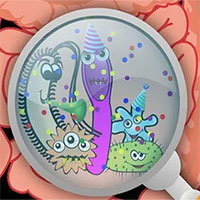

Giun móc, cái ghẻ, giun đũa, giun kim, sán lá dây... là những ký sinh trùng gây ra cho con người nhiều điều khó chịu, phiền toái, thậm chí là những bệnh tật nguy hiểm đến tính mạng.

Trong các quá trình sinh học tự nhiên, mối quan hệ cộng sinh giữa một ký sinh trùng và thân chủ có thể có những tác động có lợi, thậm chí cả việc thay đổi nhân cách con người và sự tiến hóa.

Tuy nhiên, mặt tiêu cực của mối quan hệ này thường lớn hơn nhiều so với mặt tích cực của chúng. Tạp chí New Scientist đã thống kê một số loài ký sinh trùng phổ biến nhất của con người và những tổn thương mà chúng có thể gây ra cho sức khỏe.

Dưới đây là 10 sinh vật đáng ghét ăn bám trên cơ thể người: